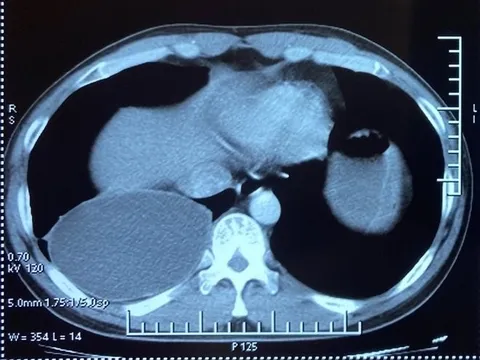

Cứu sống bệnh nhân với vết thương ở tim nguy kịch

Nam bệnh nhân 33 tuổi với vết thương ở tim nguy kịch vừa được ê-kíp bác sĩ Bệnh viện Đa khoa Trung ương Cần Thơ cứu sống.